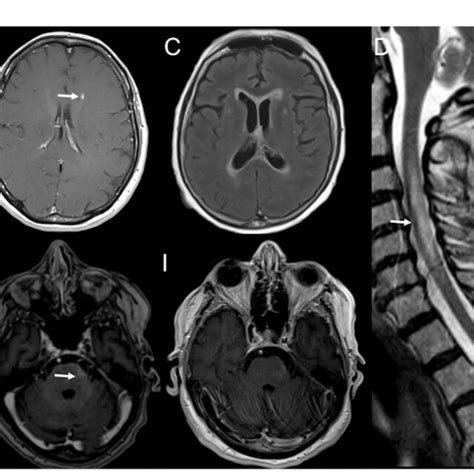

640×640

researchgate.net

FIGURE Serial brain and spinal cord MR…